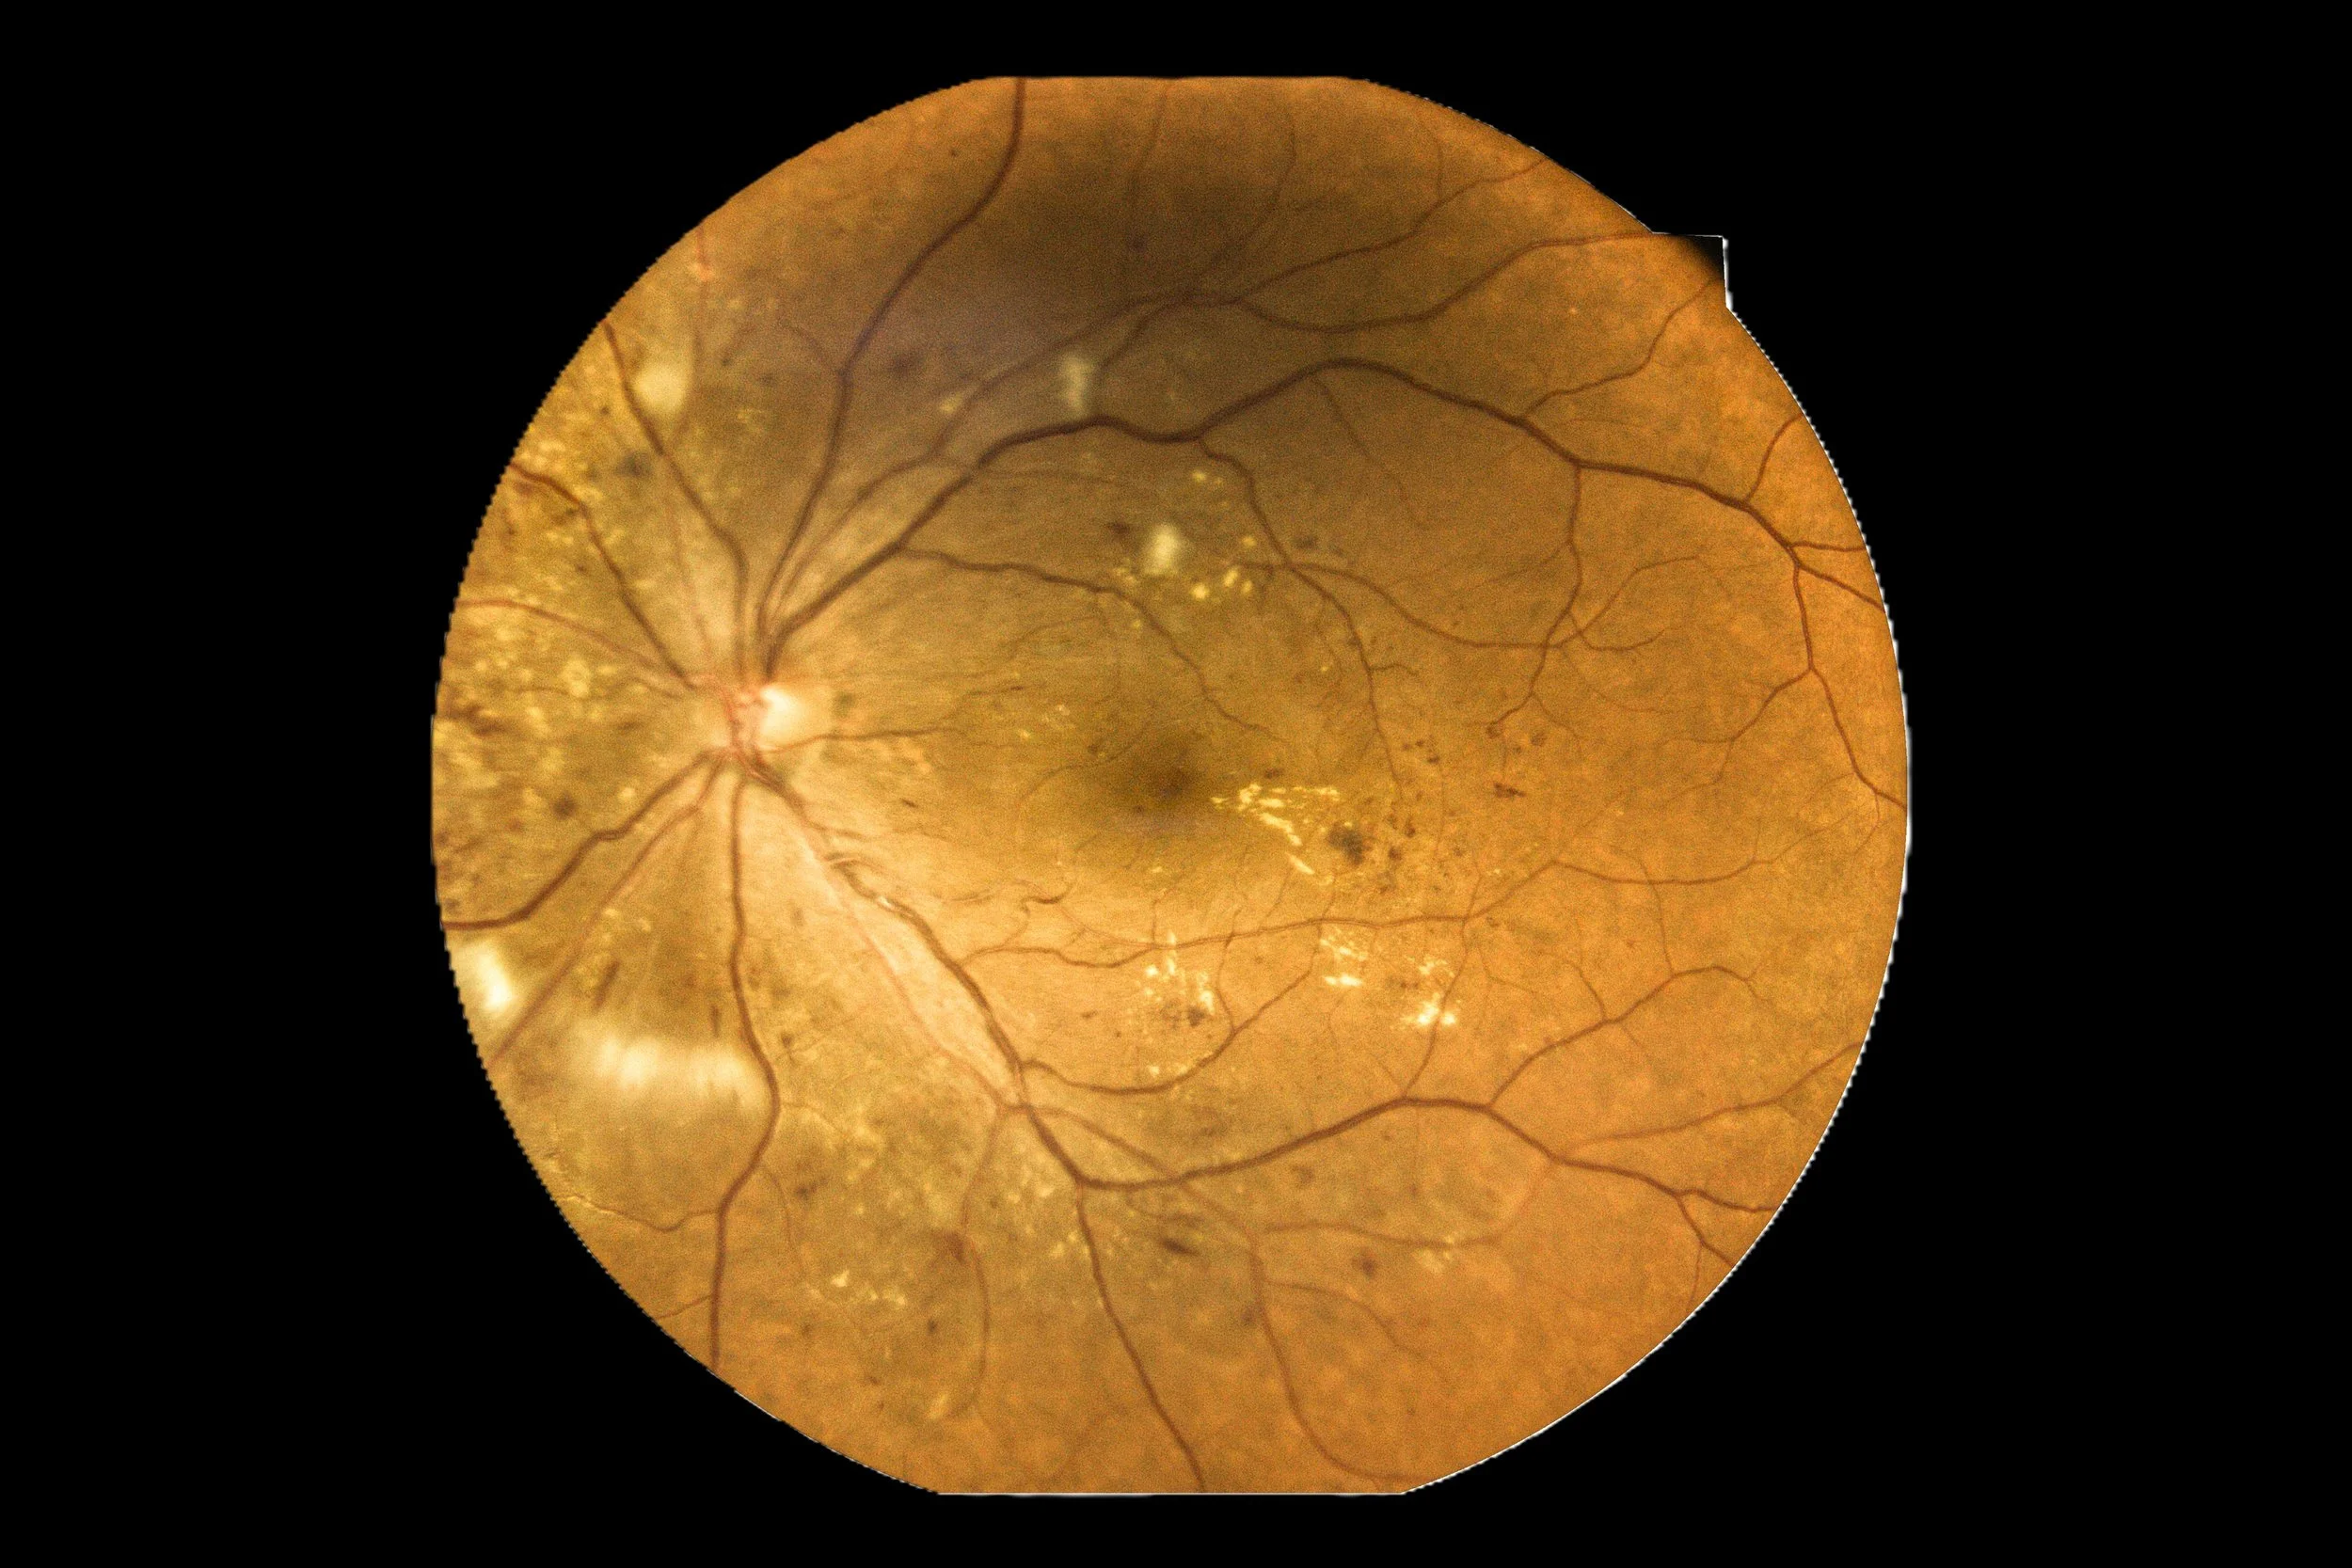

Retinal image showing the optic disc, blood vessels, and areas of pigment changes in the retina | Dr. Robert Meade | Public Speaker & Vision Consultant | Presentations about Eyes and Vision